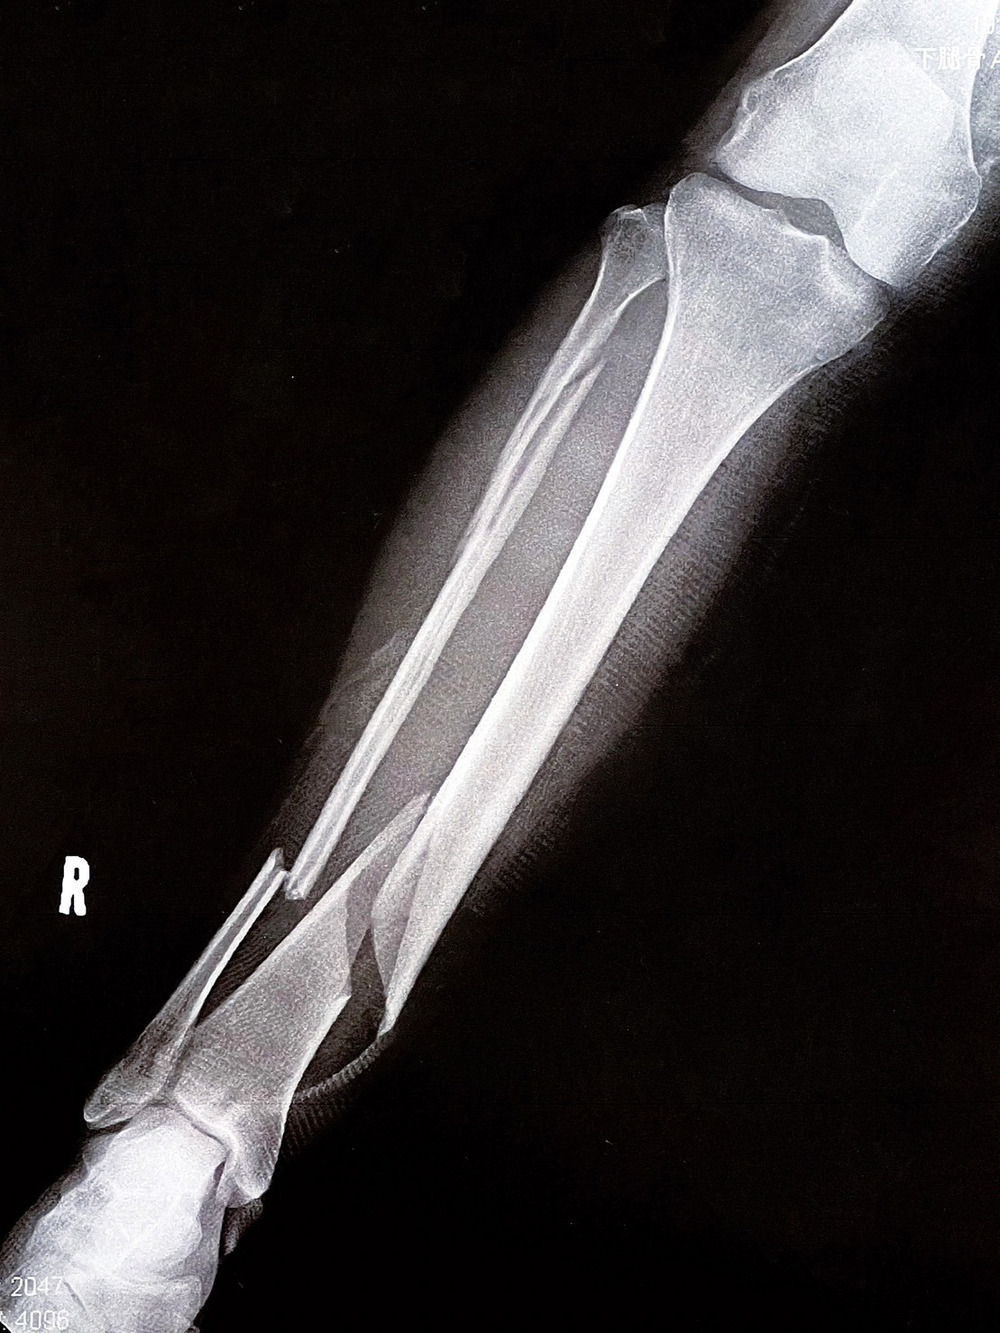

また私自身もこの年の瀬に

骨癒合不全からの骨萎縮が起こっているため

難治骨折と診断され

骨折をして1年以上経ったいまでも骨折中という

現実を受け入れられずにいまに至ります